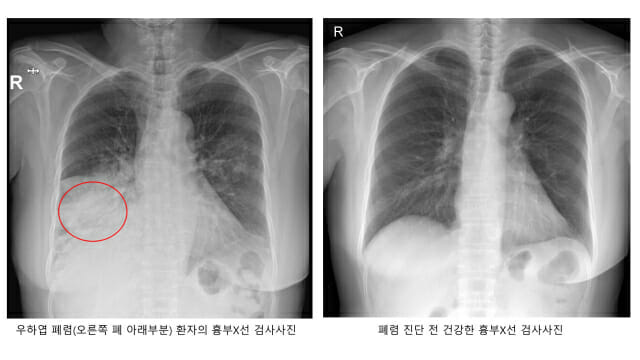

폐렴은 세균이나 바이러스가 폐로 침투해 염증이 생긴 질환을 말한다. 폐렴구균에 의한 세균성 폐렴이 흔한데, 폐렴구균은 평소에도 코와 목의 점막에 상주하기 때문이다. 몸의 면역력이 약해지면 폐·뇌·혈관·귀 등에 침투해 폐렴과 수막염 등을 일으킨다.

폐렴 초기 증상은 발열·기침·가래 등 일반 감기와 비슷하다. 그렇지만 폐렴구균이 본격적인 활동을 시작하면 고열·기침·가슴 통증·호흡곤란을 유발한다. 숨이 가빠지면 호흡수도 많아져 분당 20회를 넘게 된다.

폐렴구균에 의한 폐렴일 경우, 가래 색깔이 적갈색으로 진하게 바뀌기도 한다. 뿐만 아니다. 폐렴에 의해 폐가 손상되게 되면 산소교환 기능이 저하되게 되고, 그로 인해 혈액 속에 산소 농도가 떨어진다. 이에 따라 입술이 푸른빛으로 변하는 ‘청색증’은 폐렴 합병증의 증상이다. 이 상황에 이르면 생명이 위험할 수 있어서 반드시 병원에서 전문적인 치료를 받아야 한다.

건강한 성인은 항생제 치료와 적당한 휴식만 취하면 쉽게 나을 수 있다. 그렇지만 고령층은 폐 기능과 면역력이 떨어져 있으므로 한번 폐렴에 걸리면 중증으로 이어지는 경우가 많다. 폐렴이 악화해 호흡부전으로 이어져 인공호흡기 치료를 받거나 패혈증으로 혈압이 떨어져 치명적인 쇼크에 이르기도 한다. 다발성 장기부전은 더 위험하다.